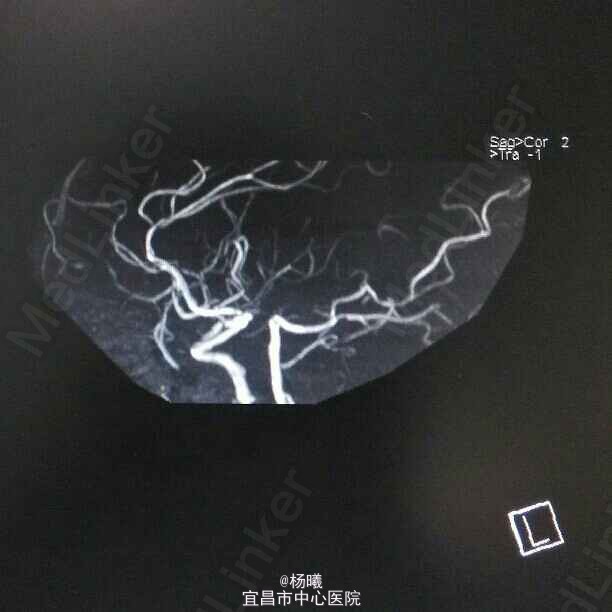

查体:BP 136/84mmHg,抬腿右下肢较左侧差,余无明显异常。 辅检:6-8 D-D 1.87,FIB 7.15,ALT 38,AST 46,GGT 37,LDL-C 4.38,铁蛋白 320,CRP 96.7,ESR 70,尿酮体1+ 6-15 PLT 469,ALT 53,GGT 50,ESR 38,D-D 0.59 血糖监测:早餐后高 彩超多普勒:升主动脉较宽,左室舒张功能减低;双侧颈动脉粥样硬化斑形成。 经颅多普勒:双侧颈内动脉、颈外动脉、左侧颈总动脉血流速度减慢;左侧锁骨下动脉、右侧大脑中动脉、大脑前动脉、左侧颈内动脉虹吸部管腔呈收缩状态;左侧颈内动脉虹吸部管腔重度狭窄;各检查动脉管腔应硬化。 头部MR、脑动脉造影MRA:脑干右侧11*12mm梗塞灶;腔隙性脑梗塞;脑萎缩;双侧额部顶部硬膜下积液;左侧椎动脉起始段及椎动脉-基底动脉汇合段管腔中度狭窄,双侧颈总、颈内外动脉、双侧大脑前中后动脉多发中-重度狭窄,动脉粥样硬化表现。

诊断:脑梗塞;高血压病3级 极高危;糖尿病 2型;动脉粥样硬化;高脂血症;慢性胃炎 治疗:依达拉奉、马来酸桂哌齐特、丹森川穹嗪注射,小牛血清去蛋白注射液;硝苯地平缓释片;阿司匹林肠溶片;阿托伐他丁钙片;阿卡波糖片。